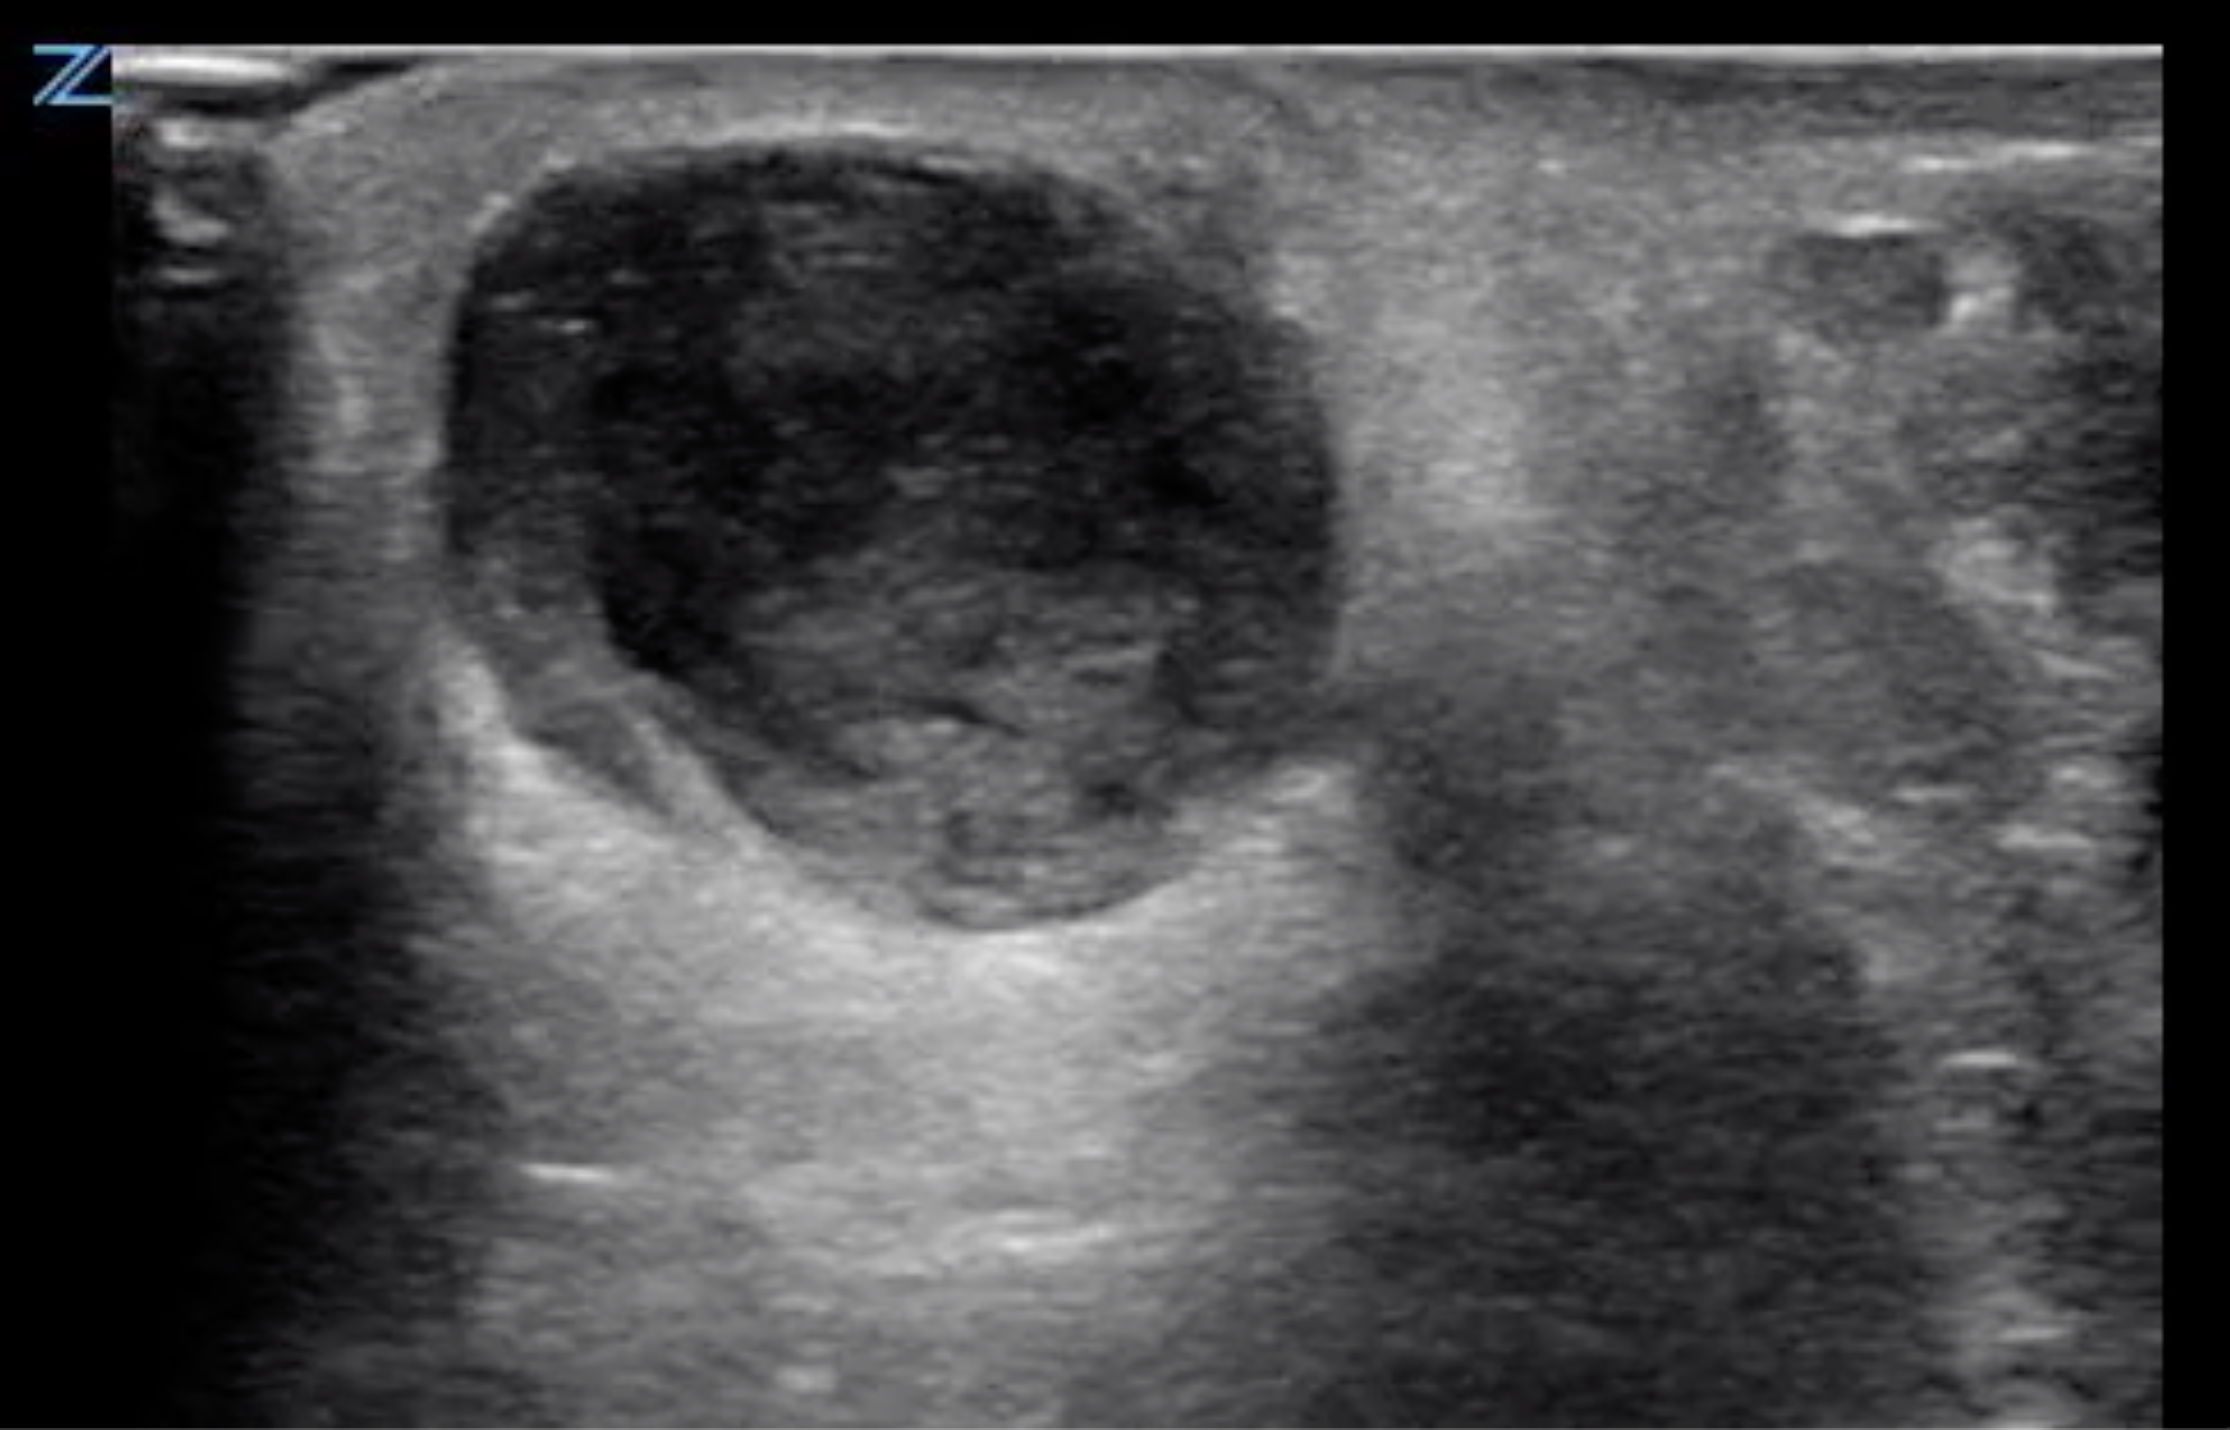

Abscess Evaluation Sonoguide